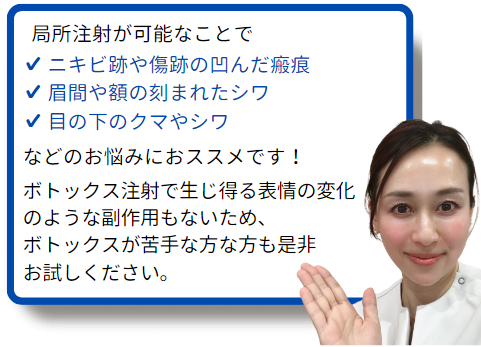

局所注射が可能

同じポリ乳酸製剤であるポテンツァ専用の製剤であるマックームは局所注射は認められていません。

プレナフィルは局所注射が可能であり、改善させたい部分に直接注射が可能です。